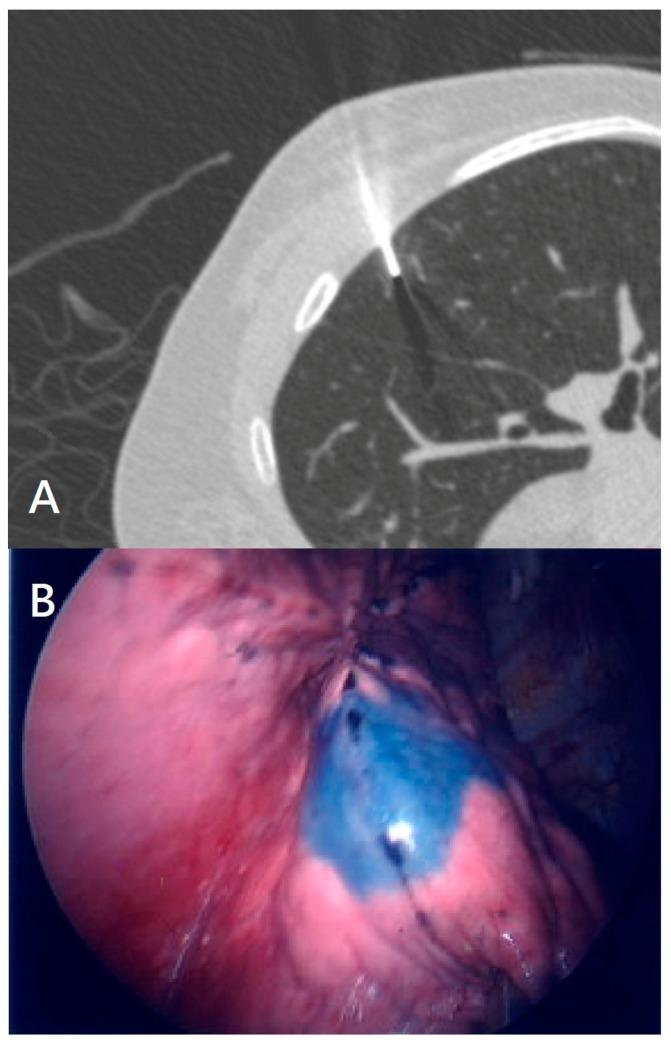

An ideal preoperative localization method is essential for the resection of small and deep-seated pulmonary nodules by video-assisted thoracoscopic surgery (VATS) in the era of low-dose computed tomography (CT) screening. This study describes a new localization method using electromagnetic navigation bronchoscopy (ENB) and compares it against conventional percutaneous CT-guided methods.

Between January 2016 and May 2018, 18 consecutive patients with a total of 27 pulmonary nodules underwent ENB localization using patent blue vital dye before thoracoscopy for lung resection at the National Taiwan University Hospital. Over the same period, 268 patients had a total of 325 pulmonary nodules localized by a CT-guided method. Propensity analysis was applied to minimize bias during comparison.

Patients were selected using a propensity-score based process, matched for potential risk factors for localization failure, to ensure equal potential prognostic factors in both groups. After matching, the ENB group had 15 patients with a total of 24 pulmonary nodules, and the CT group had 30 patients with 48 pulmonary nodules. No major procedure-related complications occurred in either group. The target pulmonary nodule was not successfully localized for one patient in the ENB group and three in the CT group. The lesions were fully excised after conversion to mini-thoracotomy. Pathological examination confirmed the accuracy of the dye staining. Analysis found a non-significant difference in the success rate of these two localization methods. However, the following parameters were significantly different: interval between localization to surgery, global time, and rate of pneumothorax (p <0.05).

In the era of minimally invasive surgery, surgeons need an efficient one-step way to manage pulmonary nodules. Patent blue vital injection with ENB guidance in the operating room is a new, effective approach to localize small, deep-seated and non-palpable pulmonary lesions, comparable with CT-guided localization.